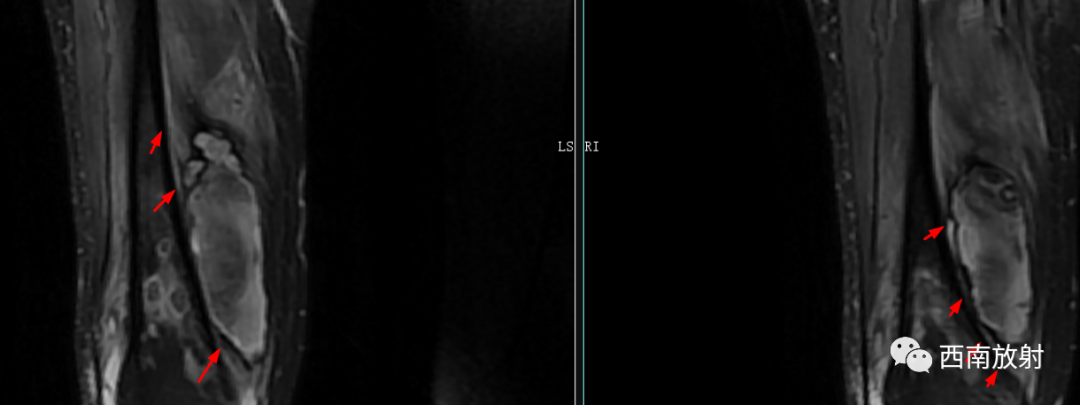

CT显示骨破坏、脓肿、死骨及骨膜增生、骨质增生硬化,呈骨小梁密度增高、模糊,髓腔密度增大、狭窄,皮质增厚。MRI显示早期骨髓内广泛分布的斑片异常信号,与邻近正常骨髓信号相比较,T1WI信号减低,T2WI信号增高,脂肪抑制T2WI 或STIR 等序列上病变显示更清楚,骨皮质周围软组织内呈弥漫分布的T1WI低信号及T2WI高信号影,边界模糊。出现骨膜反应,骨皮质不规则破坏,脓肿及死骨形成。

▲软组织脓肿